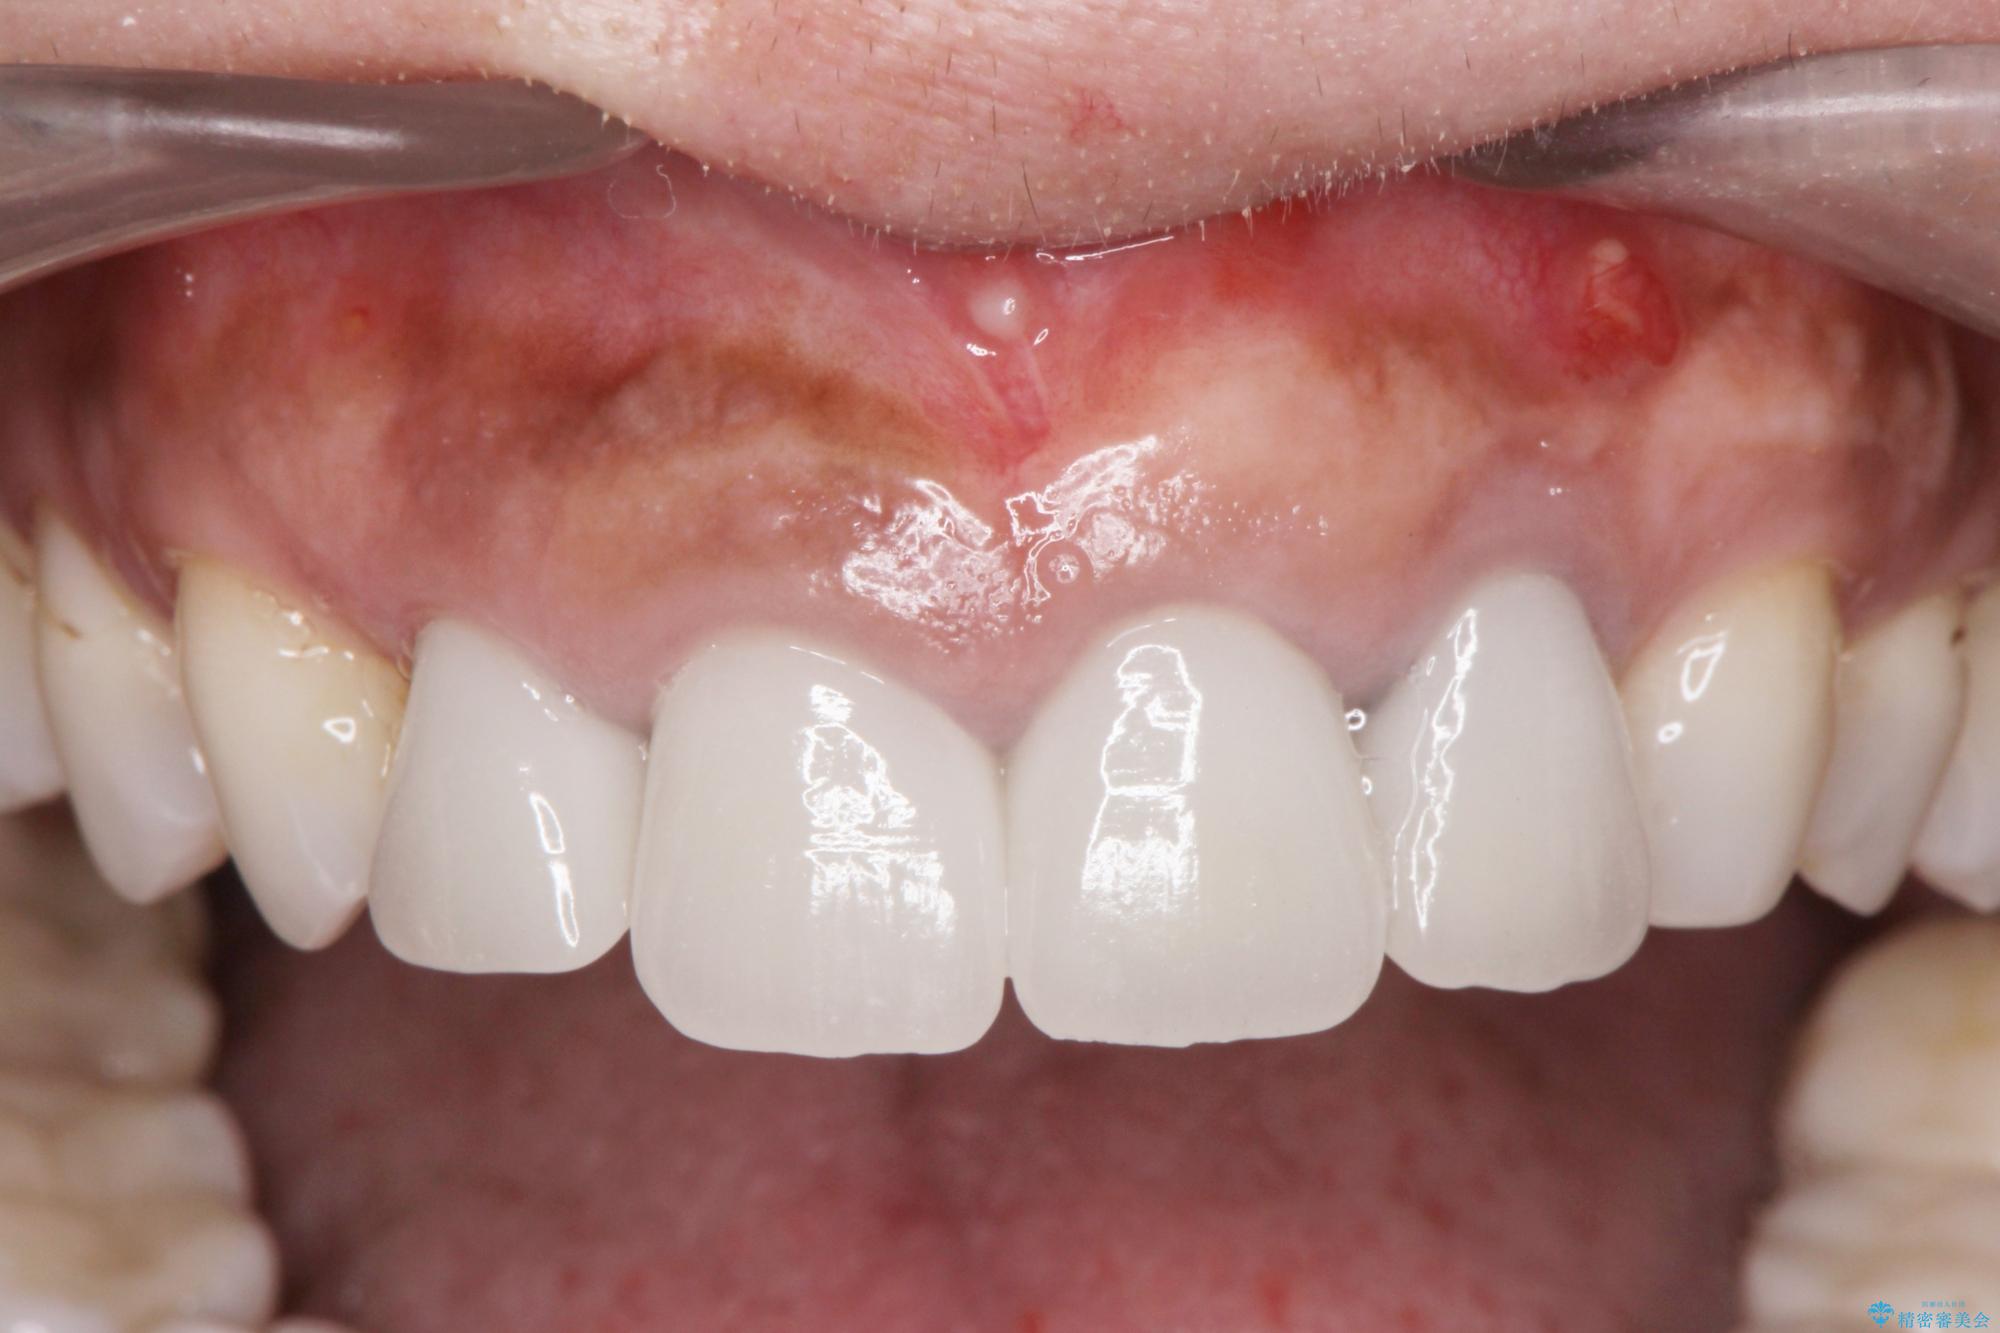

前歯がグラグラし、においもする、とのことで改善を求めて来院されました。

抜歯時に可及的に歯肉のボリュームを保つよう骨充填材とコラーゲン製剤による填塞を行い審美的かつ機能的なブリッジとなるよう治療を進めます。

歯槽堤保存術を併用したブリッジ治療 治療中画像 歯槽堤保存術を併用したブリッジ治療 治療中画像 歯槽堤保存術を併用したブリッジ治療 治療中画像 歯槽堤保存術を併用したブリッジ治療 治療中画像 歯槽堤保存術を併用したブリッジ治療 治療中画像 歯槽堤保存術を併用したブリッジ治療 治療中画像 歯槽堤保存術を併用したブリッジ治療 治療中画像